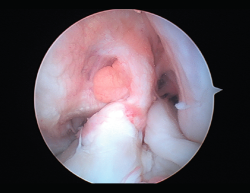

Rigidez

Una de las complicaciones más temidas, producida por un aumento del tejido fibroso, ya sea por la propia lesión (primaria) o secundaria a diferentes motivos (error técnico en la cirugía, síndrome del cíclope, inmovilización prolongada o la participación insuficiente en un programa de rehabilitación, infección, síndrome del dolor regional complejo, hematomas o sinovitis) (Figuras 7 y 8). Esta puede variar desde una ligera limitación del rango de movilidad hasta una severa artrofibrosis(21).

Figura 9. Cíclope, tejido fibroso interpuesto en la cara anterior de la plastia y que produce pinzamiento de la misma en extensión de rodilla.